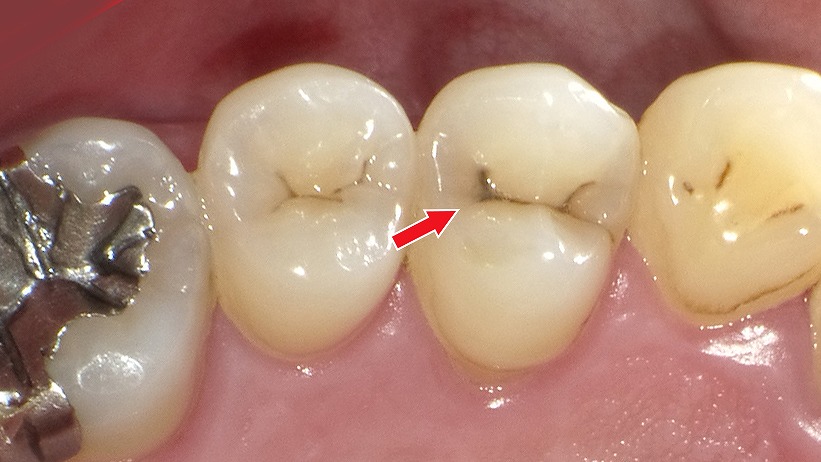

C2の場合:必要最小限の虫歯除去+CR充填

C2は虫歯がエナメル質を越えて象牙質まで進行した段階で、痛みやしみる症状が出始めることがあります。象牙質は軟らかく、C1より進行が早いため、自然な再石灰化での改善は困難です。

そのため、C2では虫歯に侵された部分のみをできる限り小さく削り、その後コンポジットレジン(CR)で修復する治療が基本となります。

この方法は、

- 健康な歯質を最大限残せる

- その日のうちに治療が完了する

- 歯の色に近く審美性に優れる

といったメリットがあり、前歯・奥歯どちらにも適応しやすい治療法です。

早期にC2を治療することで、C3(神経に達する虫歯)への進行を防ぎ、最小限の介入で歯の寿命を守ることにつながります。